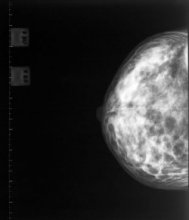

A new study has revealed the benefits of mammograms for women aged 75 years and older.

The research, published in the journal Radiology, shows that mammogram-detected breast cancers are found at an earlier stage; require less treatment; and lead to better survival rates.

Renewed questions have been raised about the value of mammograms after a Canadian study suggested that it does not reduce the number of deaths from breast cancer.

BCAC chair Libby Burgess says while the latest research is thought-provoking, it should in no way prompt New Zealand women to stop getting their free mammograms every two years through BreastScreen Aotearoa.